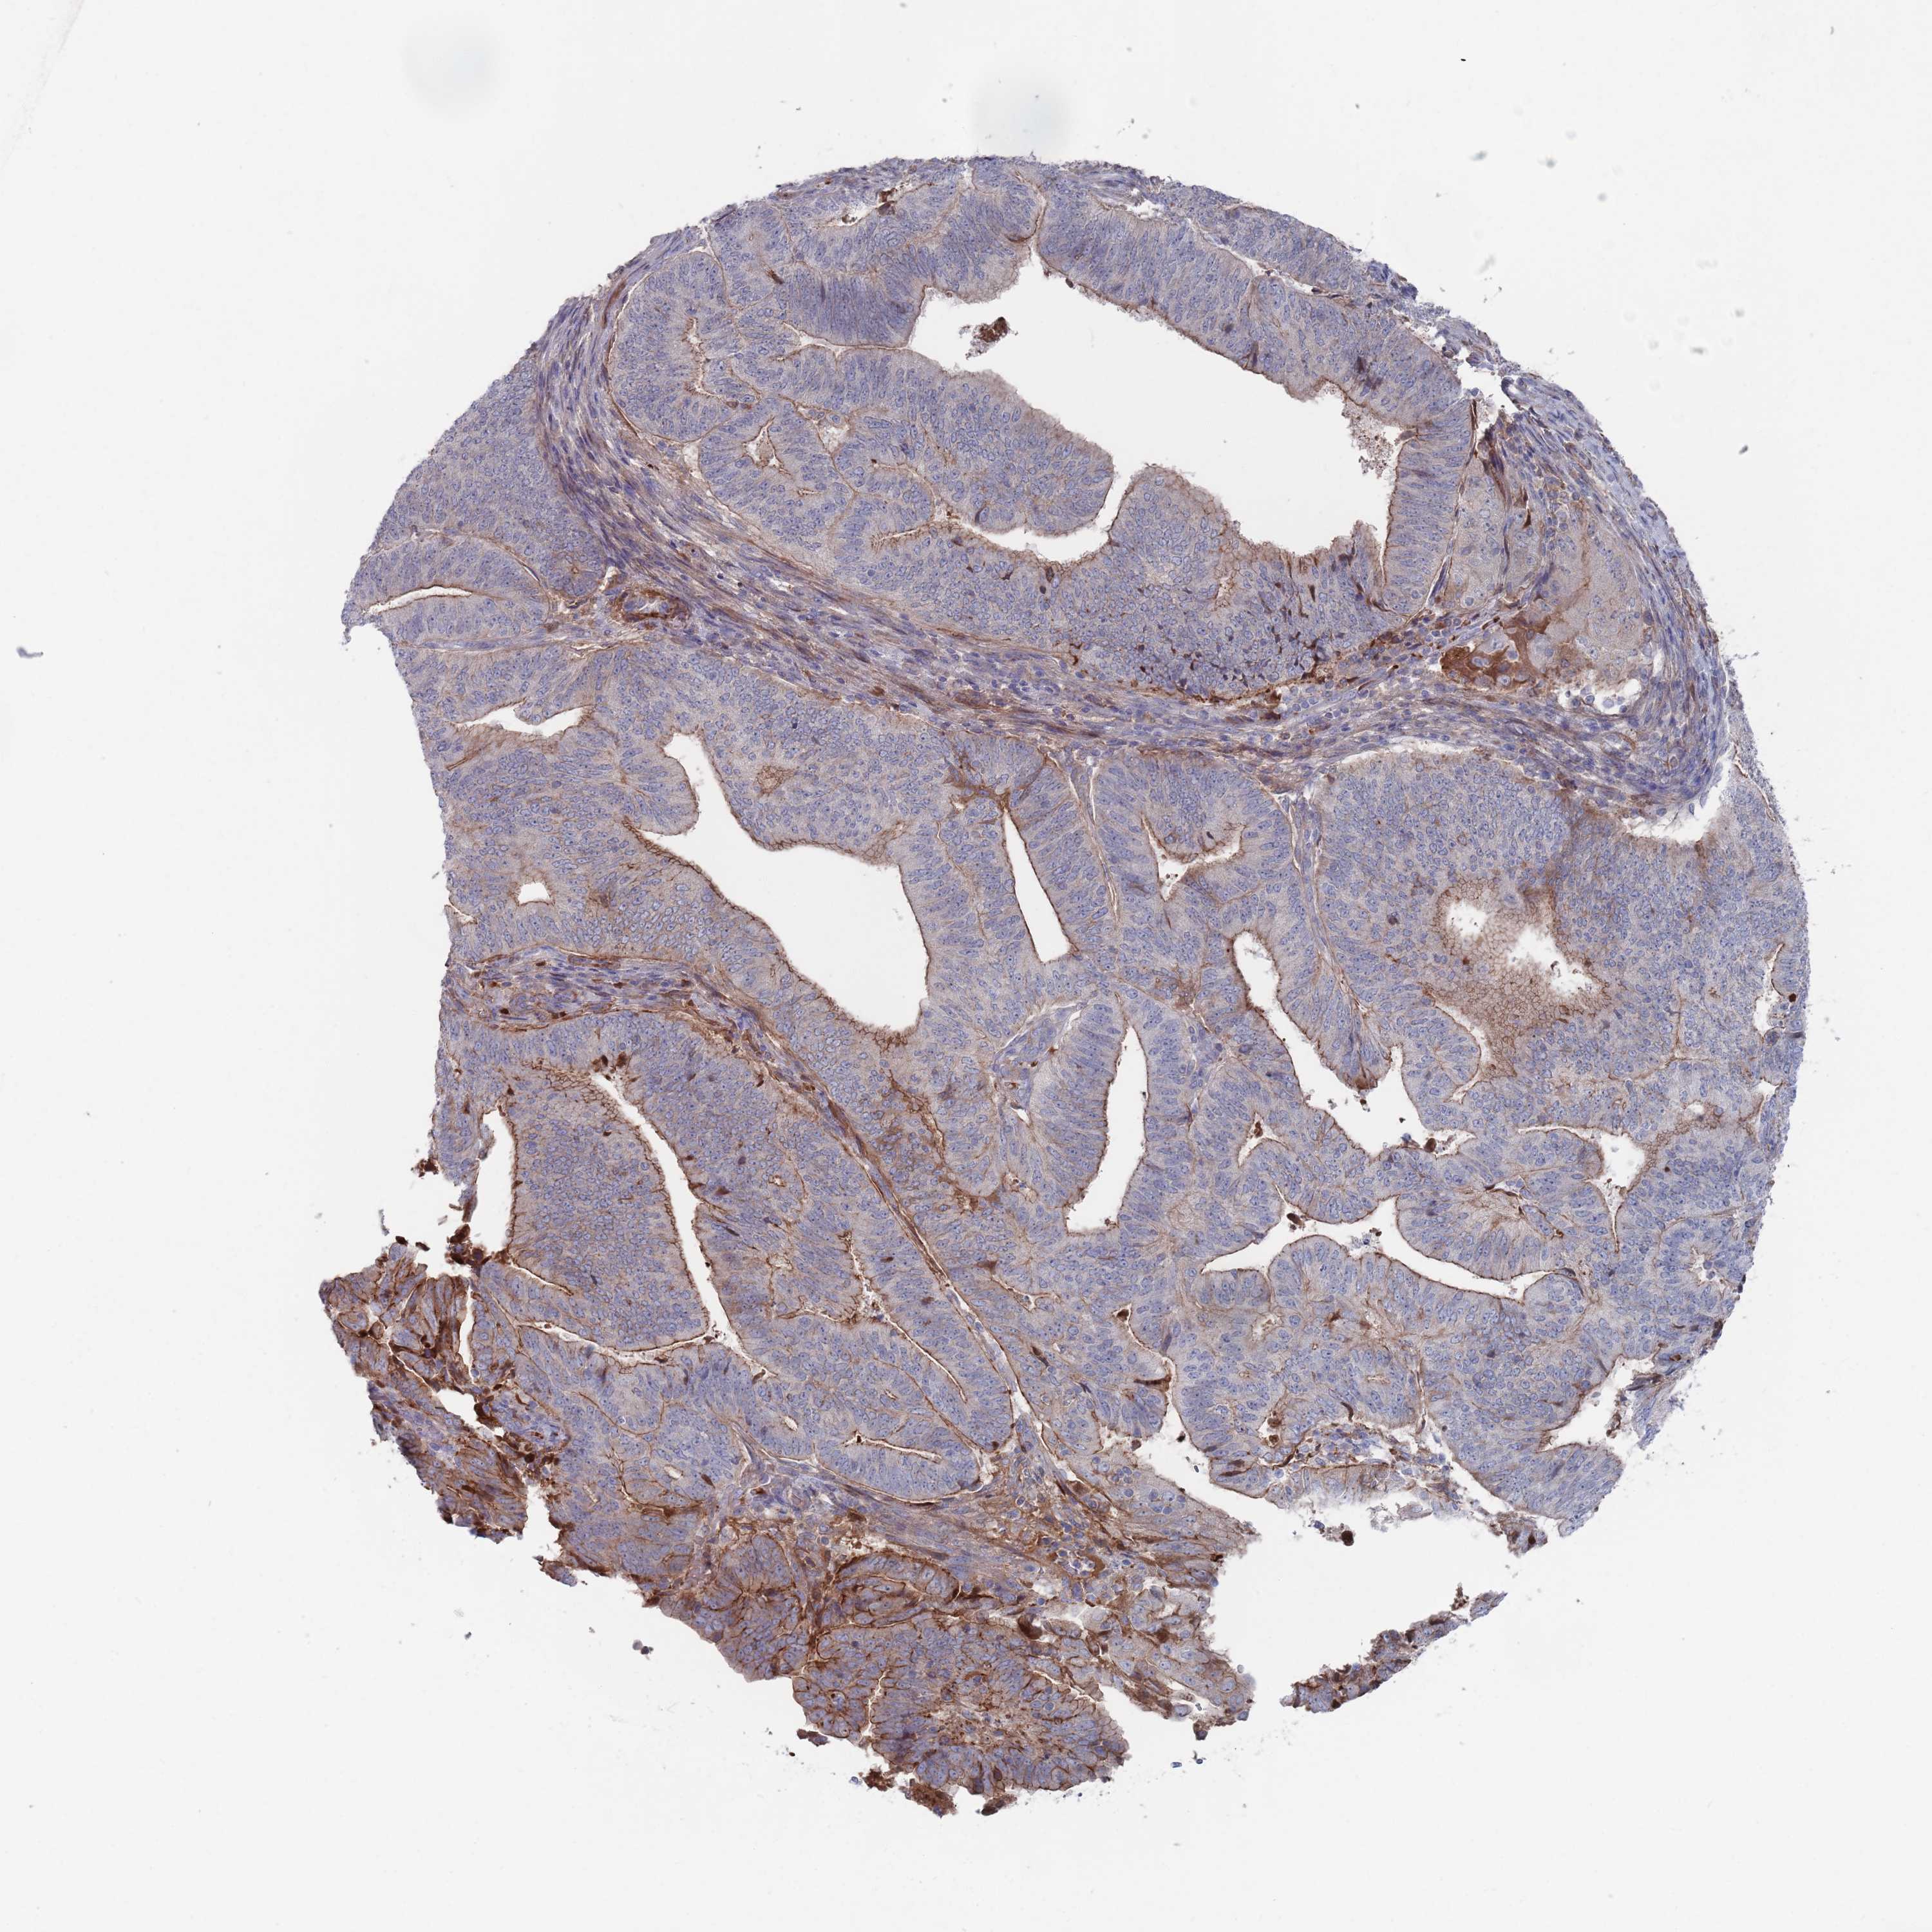

ENDOMETRIAL CANCER - Protein expressioni

A mouse-over function shows sample information and annotation data. Click on an image to view it in a full screen mode. Samples can be filtered based on level of antibody staining by selecting one or several of the following categories: high, medium, low and not detected. The assay and annotation is described here.

Note that samples used for immunohistochemistry by the Human Protein Atlas do not correspond to samples in the TCGA dataset.

Antibody stainingi

Antibody staining in the annotated cell types in the current human tissue is reported as not detected, low, medium, or high, based on conventional immunohistochemistry profiling in selected tissues. This score is based on the combination of the staining intensity and fraction of stained cells.

Each image is clickable and will lead to virtual microscopy that enables deeper exploration of all samples and also displays staining intensity scores, fraction scores and subcellular localization as well as patient and tissue information for each sample.

Antibody HPA042978

Antibody HPA048473

Staining

High

Medium

Low

Not detected

Intensity

Strong

Moderate

Weak

Negative

Quantity

>75%

75%-25%

<25%

None

Location

Nuclear

Cytoplasmic/membranous

Cytoplasmic/membranous,nuclear

Adenocarcinoma, NOS